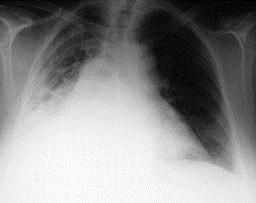

问题 男,54岁,发热、胸痛一月余,继往有酗酒史,请结合CT图像选择最可能的诊断 ( )

选项 A、肺囊虫病 B、肺癌 C、肺脓肿 D、大叶性肺炎 E、脓胸

答案 E